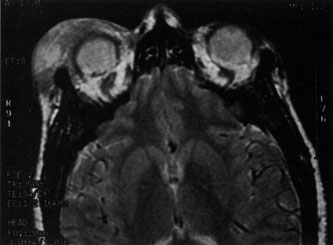

Magnetic resonance imaging (MRI) is purported to be more useful than CT in the diagnosis of preseptal cellulitis. It is less reliable at diagnosing the subtle signs of muscle enlargement and periscleritis and thus is not as useful in differentiating orbital cellulitis from other inflammatory orbital diseases.71 On MRI with gadolinium contrast, orbital cellulitis may show a smearing or linear streaking of the normal fat shadows on T2-weighted images. MRI is excellent for demonstrating localized fluid collections such as abscesses. It is not helpful in distinguishing a transudate from an exudate, because both appear liquid and are of low intensity on T1-weighted images and bright on T2-weighted images (Fig. 19).

Fig. 19. Magnetic resonance image of preseptal cellulitis with anterior abscess formation.